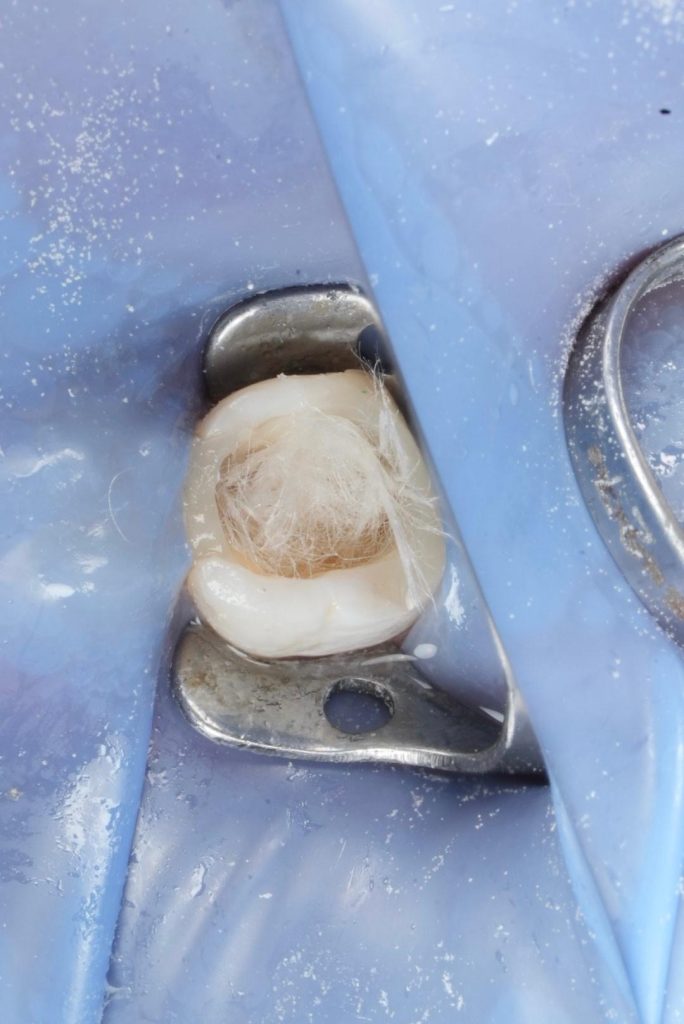

- Rubber dam isolation applied throughout the procedure.

- Existing composite removed; defective margins corrected.

- Previous root filling material removed using rotary retreatment files and solvents.

Deep Margin Elevation (DME)

- Distal subgingival margin elevated using flowable resin (GC EverX Flow / Equivalent).

- Garrison sectional matrix used to ensure tight proximal contact and emergence profile.

- Adhesive protocol respected to optimise bond.